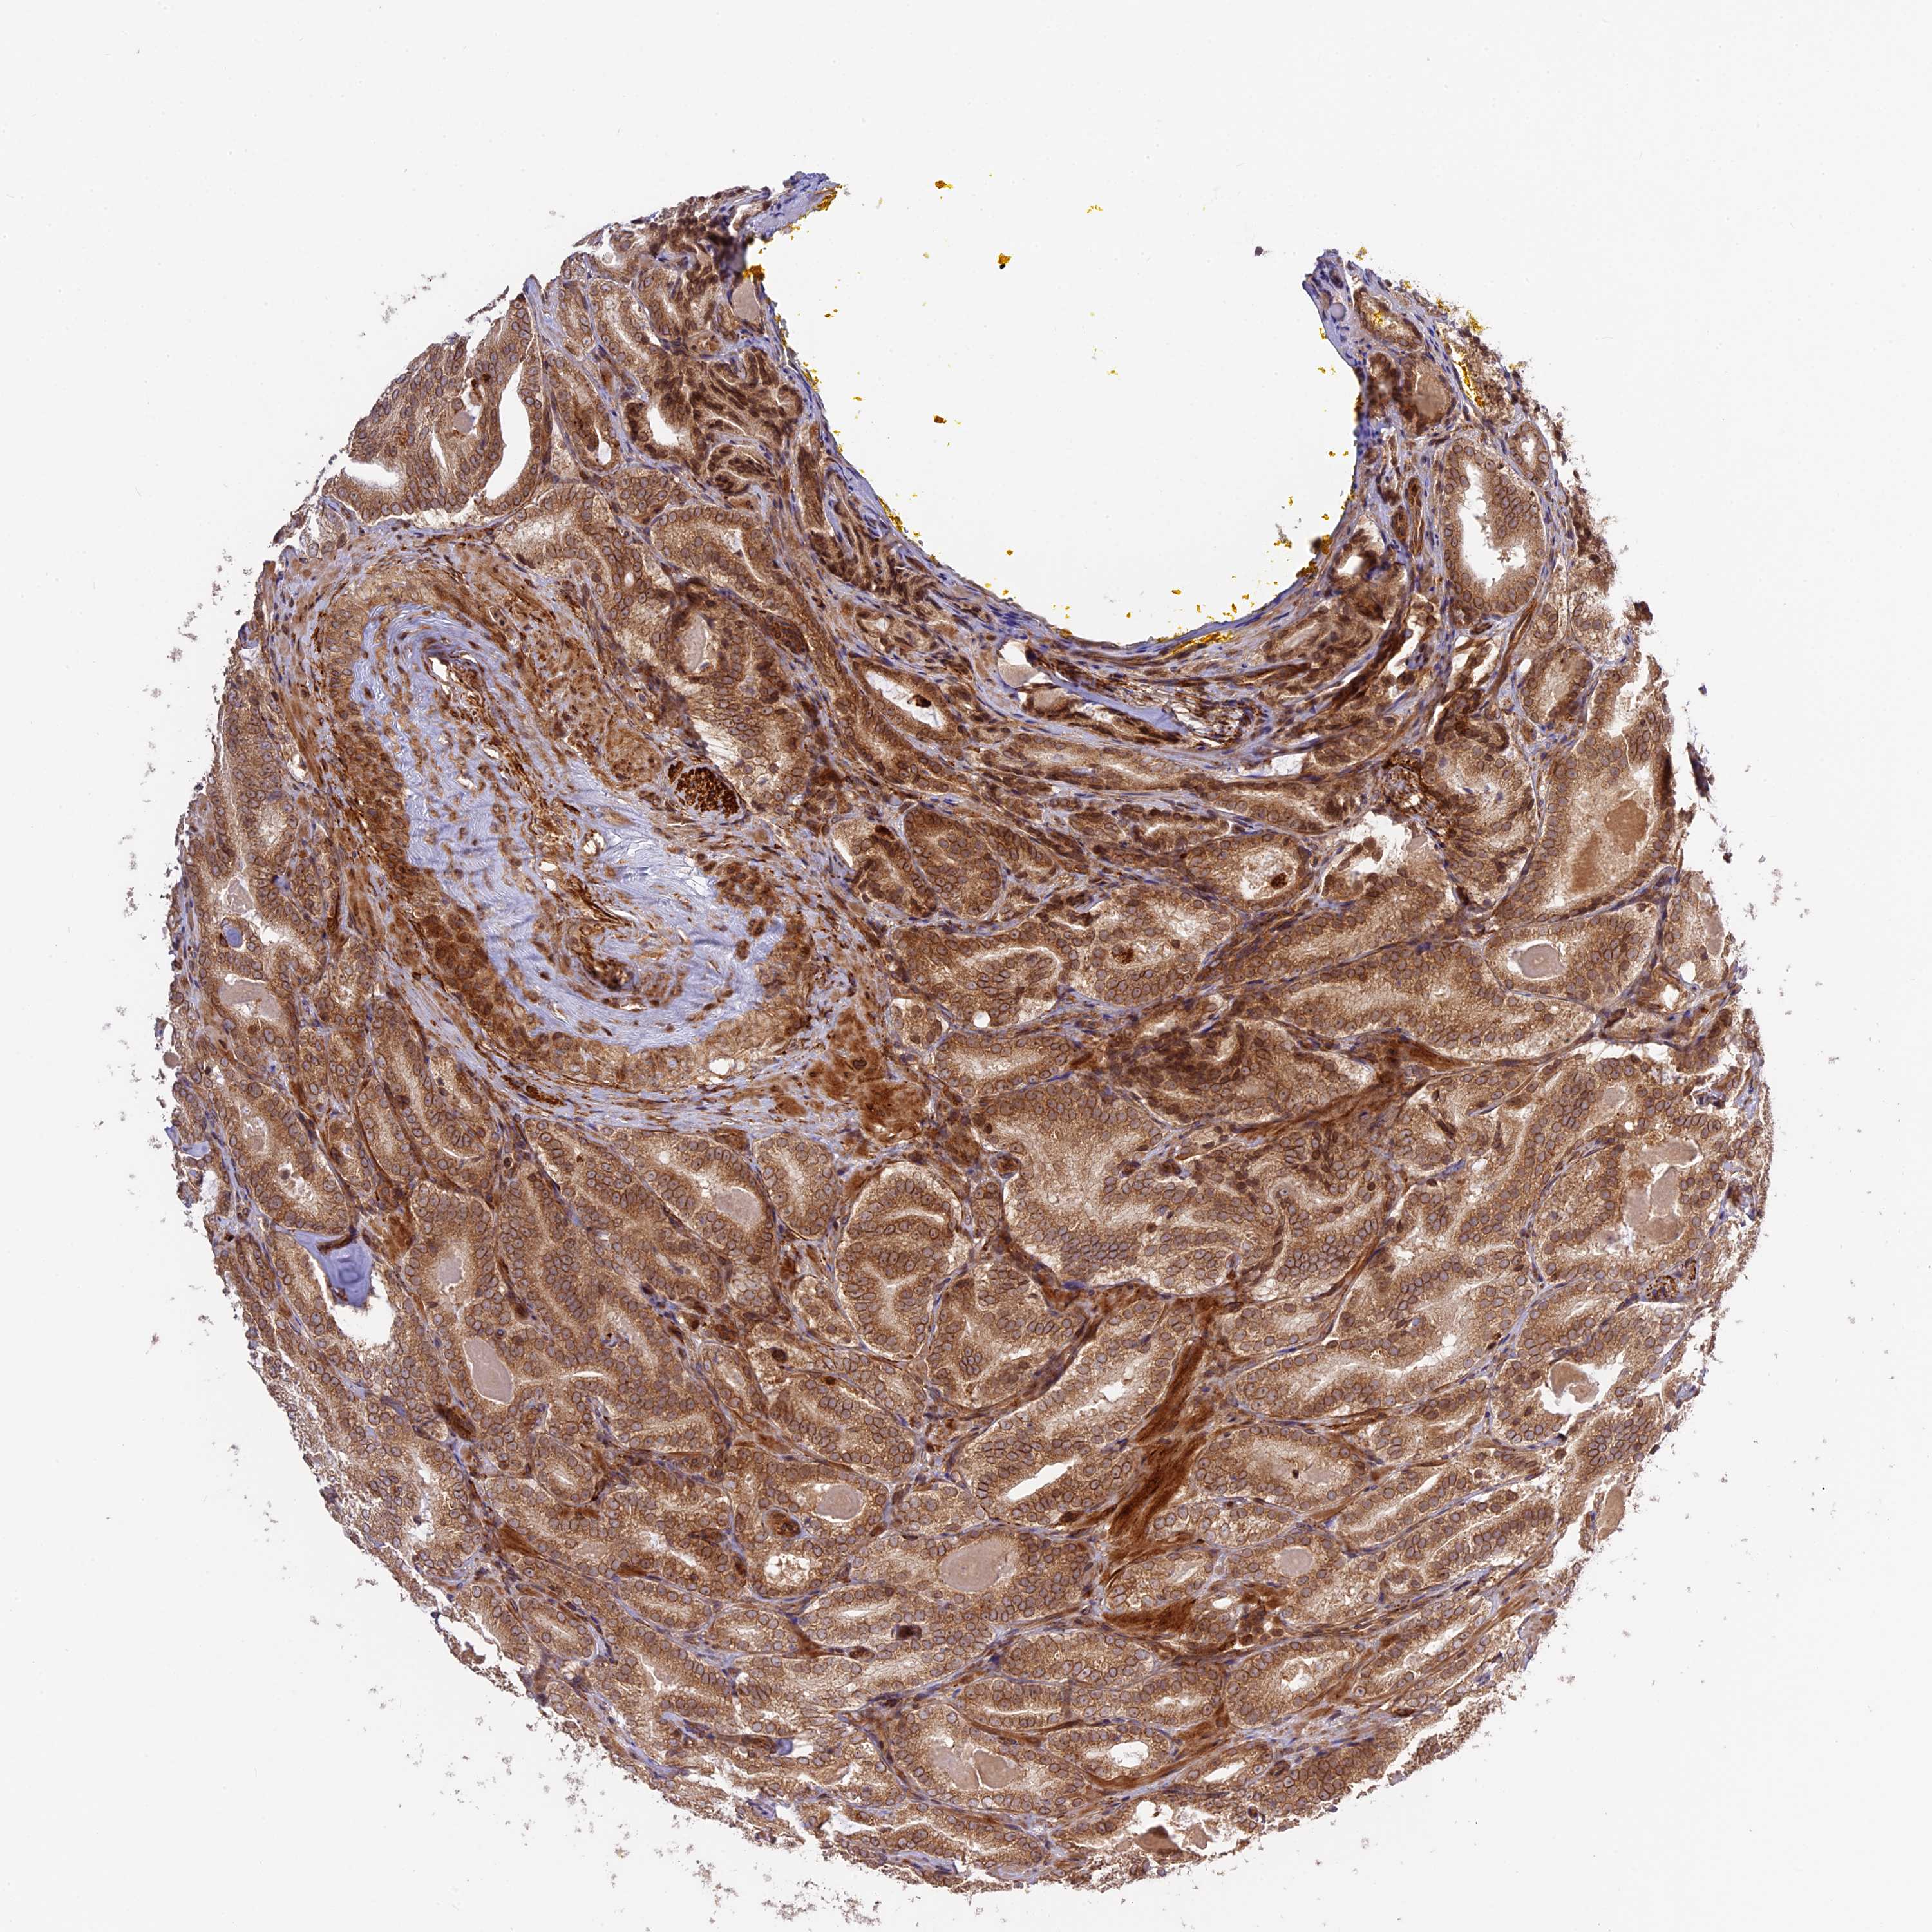

PROSTATE CANCER - Protein expressioni

A mouse-over function shows sample information and annotation data. Click on an image to view it in a full screen mode. Samples can be filtered based on level of antibody staining by selecting one or several of the following categories: high, medium, low and not detected. The assay and annotation is described here.

Antibody stainingi

Antibody staining in the annotated cell types in the current human tissue is reported as not detected, low, medium, or high, based on conventional immunohistochemistry profiling in selected tissues. This score is based on the combination of the staining intensity and fraction of stained cells.

Each image is clickable and will lead to virtual microscopy that enables deeper exploration of all samples and also displays staining intensity scores, fraction scores and subcellular localization as well as patient and tissue information for each sample.

Antibody HPA039533

Antibody HPA040355

Staining

High

Medium

Low

Not detected

Intensity

Strong

Moderate

Weak

Negative

Quantity

>75%

75%-25%

<25%

None

Location

Nuclear

Cytoplasmic/membranous

Cytoplasmic/membranous,nuclear

Adenocarcinoma, High grade

Adenocarcinoma, Low grade